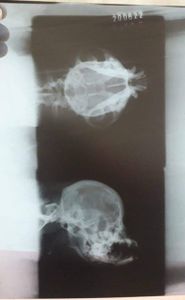

Cãozinho acidentado precisa de cirurgia do maxilar

Meu cãozinho foi atacado por outros animais e agora está precisando de uma cirurgia pq seu maxilar está solto.

Os custos c medicamentos e cirurgia chegam aos 3mil reais.